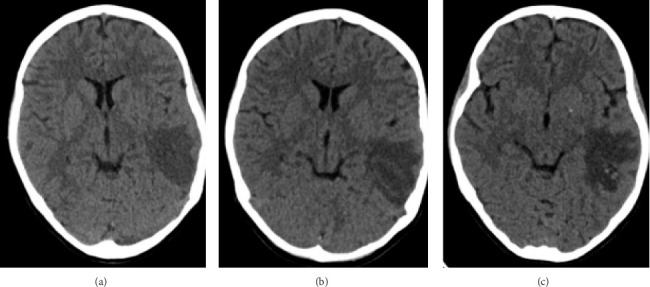

我们报告了一个10岁的女孩谁有一个非典型脱髓鞘疾病作为她的神经精神狼疮的表现。患者有4年的系统性红斑狼疮病史,10岁时出现发热和头痛,病情一度缓解。体格检查显示脑膜炎。感染性脑膜炎的广泛微生物检查未见结果。在脑磁共振成像(MRI)上发现广泛的白质高信号。在我们病例的初始阶段,由于中枢神经系统感染和狼疮的神经精神表现难以区分,在等待微生物检查结果的同时,经验性地给予静脉注射免疫球蛋白一个疗程,而不是大剂量的皮质类固醇。在开始静脉注射免疫球蛋白而不使用脉冲皮质类固醇后,发热和头痛很快消退。在活动性神经症状缓解后,她被给予6个月剂量的静脉注射免疫球蛋白(2g /kg/周期)和6个双周剂量的静脉注射环磷酰胺(500mg /m2/月)。间歇MRI显示白质高信号消退。尽管最初的表现是广泛的脱髓鞘疾病,但她成功地缓解了,没有残余的神经系统后遗症。

We reported a 10-year-old girl who had an atypical demyelinating disease as the presentation of her neuropsychiatric lupus. The patient had a 4-year history of systemic lupus erythematosus which had been on remission until she presented with fever and headache at the age of 10 years. Physical examination showed meningism. Extensive microbiological workup for infective meningitis was unrevealing. There was a radiographic finding of an extensive white matter hyperintensity on the magnetic resonance imaging (MRI) of the brain. At the initial stage of our case, as it was difficult to differentiate between infection of the central nervous system and neuropsychiatric manifestation of lupus, a course of intravenous immunoglobulin was given empirically instead of high-dose corticosteroid while awaiting the microbiological workup results. The fever and headache subsided shortly after commencement of intravenous immunoglobulin without use of pulse corticosteroid. After the active neurological symptoms remitted, she was given a total of six monthly doses of intravenous immunoglobulin at 2 g/kg/cycle and six biweekly doses of intravenous cyclophosphamide at 500 mg/m2/month. Interval MRI showed resolution of the white matter hyperintensity. Despite the extensive demyelinating disease on initial presentation, she remitted successfully without residual neurological sequelae.